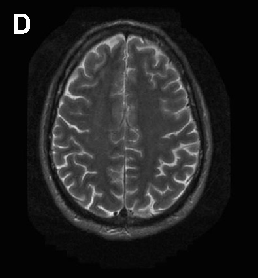

In ChAc and MLS, electroneurography may demonstrate sensorimotor axonal neuropathy whereas electromyography may show neurogenic as well as myopathic alterations. Electroencephalographic findings are not specific and may comprise normal findings, generalized slowing, focal slowing, and epileptiform discharges. Neuroradiologically, there is progressive striatal atrophy especially affecting the head of caudate nucleus and impaired striatal glucose metabolism similar to that seen in HD (Figure 2) [24,26]. Voxel-based morphometry of MRI scans in ChAc shows specific involvement of the head of the caudate nucleus [41,42]. Neurodegeneration in both core NA syndromes affects predominantly the caudate nucleus, putamen and globus pallidus. In ChAc, thalamus and substantia nigra are also involved. In contrast to HD, there is no significant cortical pathology [8,43-45]. Neuropathological findings consist of neuronal loss and gliosis of variable degree in these regions, but no inclusion bodies of any nature or other distinct neuropathological features have as yet been detected.

Cerebral MRI is often diagnostic in PKAN, and the diagnosis is confirmed by analysis of the PANK2 gene (Figure 2). Analysis of the JPH3 gene CTG expansion is useful in patients of African ancestry with suspected HDL2.

Figure 2 Neuroimaging. ChAc. Coronal FLAIR- (A) and axial T1-weighted (B) images demonstrate moderate atrophy of the caudate nucleus. MLS. Axial T2-weighted images demonstrate moderate atrophy of caudate nucleus and putamen (C) but no relevant cortical atrophy (D). HDL2. Axial FLAIR- (E) and coronal T1-weighted images (F) demonstrate atrophy of the caudate nucleus and the fronto-temporal cortex. In addition, FLAIR images show periventricular white matter hyperintensities (courtesy of Nora Chan, MD, UCLA, Los Angeles, USA). PKAN. T2-weighted fast spin echo (G) and T1-weighted (H) brain MRI scans from a child with PKAN demonstrating the “eye of the tiger” sign (courtesy of Susan J. Hayflick, MD, Oregon Health and Science University, Portland, Oregon, USA)